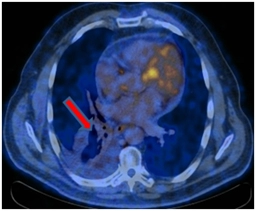

ПЭТ-КТ от 12.01.2017. В правом легком определяется мягкотканое образование метаболическим размером 30×24 мм с кальцинатом в структуре SUVmax=21,36, перекрывающий просвет промежуточного бронха справа сразу за уровнем ответвления среднедолевого бронха с формированием картины «культи бронха» – в бифуркационном лимфатическом узле до 20 мм SUVmax=4,77.